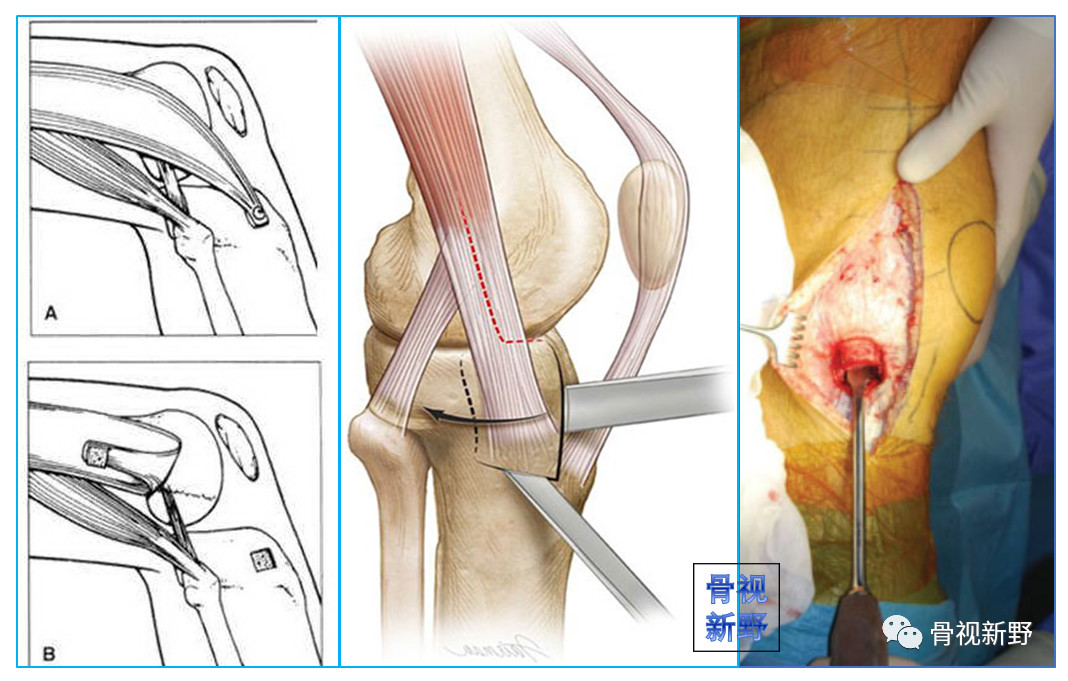

swashbuckler入路

在胫骨结节外侧沿髌骨外侧缘行皮肤切口,延伸至髌骨的外上角,切口长度约12-15cm。

锐性分离膝关节部位皮瓣直至暴露外侧髌韧带,沿髌韧带作梯形手术切口,暴露膝关节,如图1,该切口远端起始于髌腱胫骨止点外侧,沿髌骨边缘的髌韧带延伸至股外侧肌肌腹。

后按一下四个步骤进行股骨远端暴露:1. 使用手指将髌腱从髌后脂肪垫上钝性分离;2. 完全切除髌后脂肪囊和滑囊至半月板韧带水平,注意此时需保护半月板和半月板间韧带;3. 完全松解髌韧带远方胫骨结节止点;4. 最后松解髌韧带上方以获得进入髌上囊的空间。

在胫骨近端靠近内侧半月板水平放置霍夫曼拉钩以牵开髌骨,在髌上囊水平放置另一个霍夫曼拉钩牵开近段股中间肌完成微创swashbuckler入路。

沿髌韧带所作的梯形手术切口,注意该梯形手术切口仍位于髌韧带内而未延伸至股外侧肌腹

微创swashbuckler入路与股骨轴线呈30度角所拍摄的图片。图中整个股骨远端关节面得到接近完整的暴露